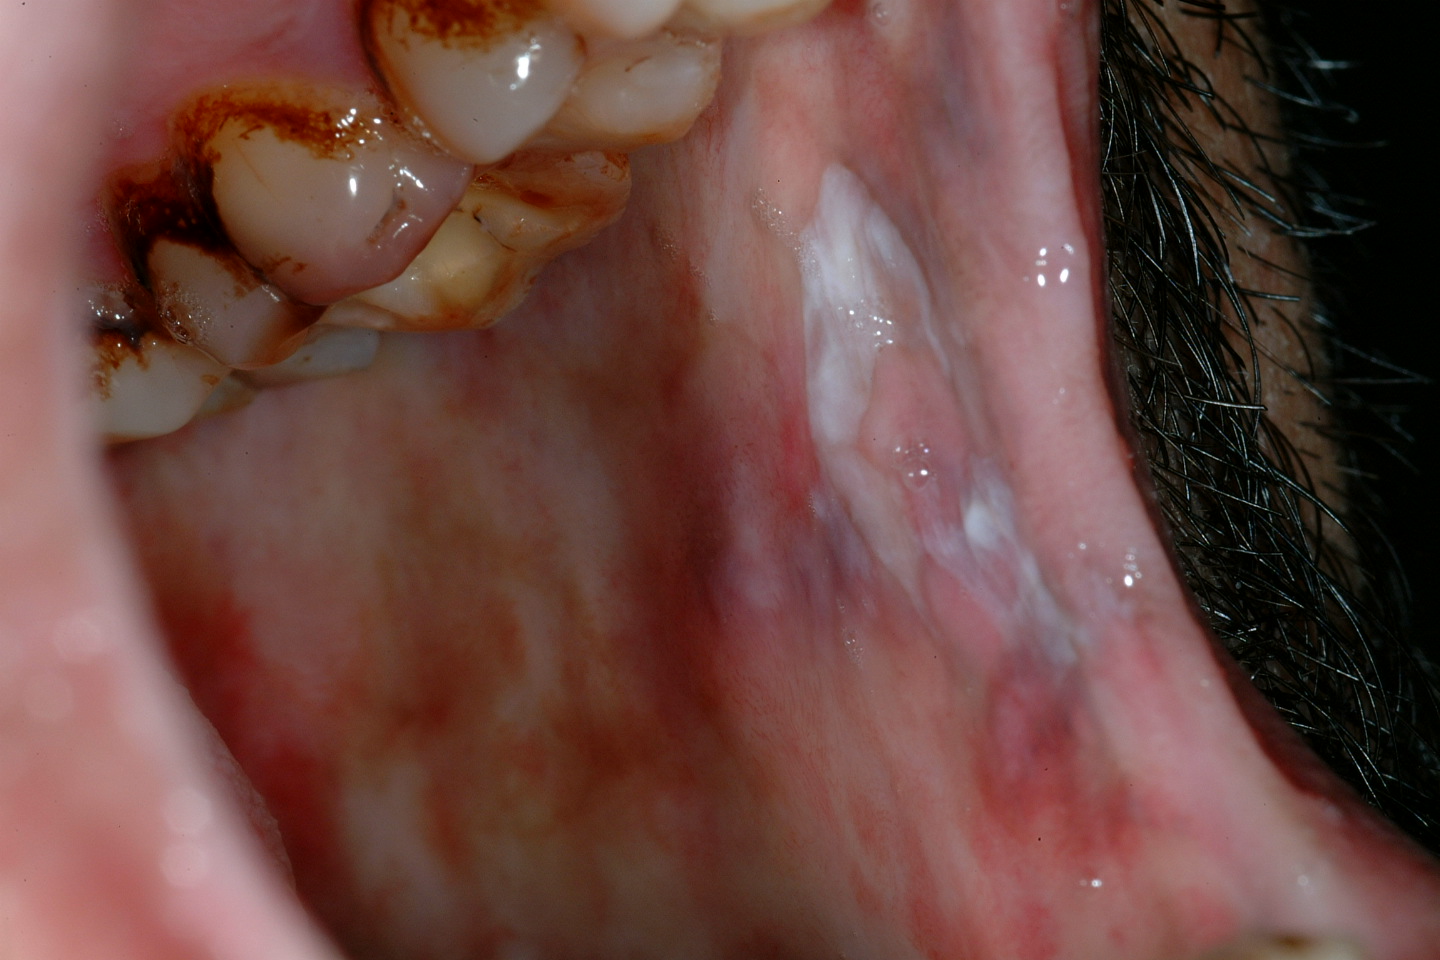

Submucous fibrosis is a progressive lesion forming bands of scarred tissue (fibrosis) beneath the mucosa (see Figure 4). Submucous fibrosis is associated with epithelial dysplasia and a quoted risk for malignant transformation of approximately 5 %. The strands of scarred tissue (fibrosed bands) can lead to severe trismus (difficulty opening the mouth). Submucous fibrosis is strongly associated with chewing habits of areca nuts, gutka and betel – common on the Indian subcontinent.